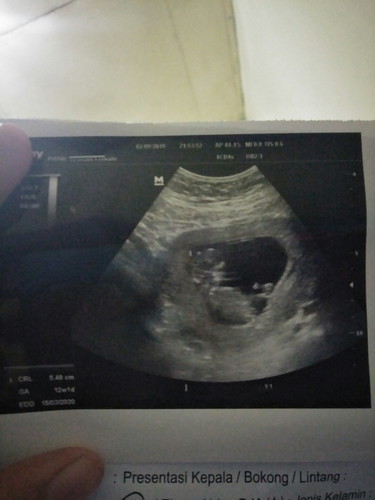

USG KE DUA DAN KE TIGA BEDA UMUR KANDUNGAN

Malam bunda Mau nanya, emang usg suka beda gt ya? Soalnya anak pertama jadi gatau Usg kedua umur kandungan 7minggu, aku itung itu harusnya pas balik usg umur kandungan baru 11minggu tapi ternyata usg ke tiga 12minggu 1hari.. Kenapa bisa beda ya? Saya tadi mau nanya lupa karena sudah kemaleman banget, jam10 baru keluar dari bidan Terimakasih bunda bunda